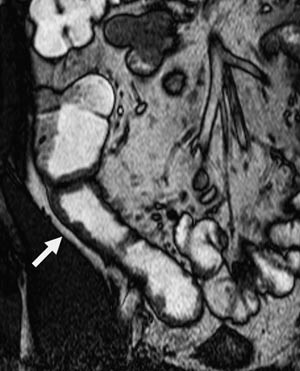

Vanlige MR-funn ved Crohns sykdom er fortykket tarmvegg (fig 5). Mer overflatiske forandringer i slimhinnen blir ikke optimalt fremstilt, men dypere ulcuser blir fremstilt, og dette er tegn på aktiv inflammasjon (fig 6). Både fibrose og aktiv inflammasjon i tarmveggen lader opp etter intravenøs kontrast. Det typiske for aktiv inflammasjon er en kraftig og lagdelt kontrastoppladning (fig 7), men den kan også være mer homogen.

Vår erfaring med MR av tynntarm skriver seg i hovedsak fra undersøkelser av pasienter med Crohns sykdom. Det finnes flere studier der man har sammenliknet MR av tynntarm med sonde og røntgen tynntarm med sonde med kliniske funn hos pasienter med denne sykdommen (1) – (6). Disse studiene viser at MR-undersøkelse er like bra som konvensjonell tynntarmsrøntgen for fremstilling av dype ulcuser og stenoser. Sensitiviteten var 100 % og spesifisiteten 75 % for fremstilling av dype ulcuser (3). Stenose ble påvist med en sensitivitet og en spesifisitet på 100 % (2, 3). Forandringer utenfor tarmen, som abscess og fistel, ble påvist i større grad med MR enn med konvensjonell røntgen og med en sensitivitet på henholdsvis 80 % og 70 % (4). I en studie fra 2004 ble MR-funn og røntgenfunn proksimalt for terminale ileum sammenliknet hos pasienter med kjent Crohns sykdom i colon eller terminale ileum (6). Det var samme funn i terminale ileum hos 23 av 25 pasienter med MR og med endoskopi. Ved hjelp av MR ble det påvist flere lesjoner proksimalt for terminale ileum enn det som ble påvist med konvensjonell røntgen. Overflatiske ulcuser er vanskelig å fremstille på MR pga. for lav bildeoppløsning. Disse fremstilles bedre med konvensjonell røntgen av tynntarm med sonde (3).